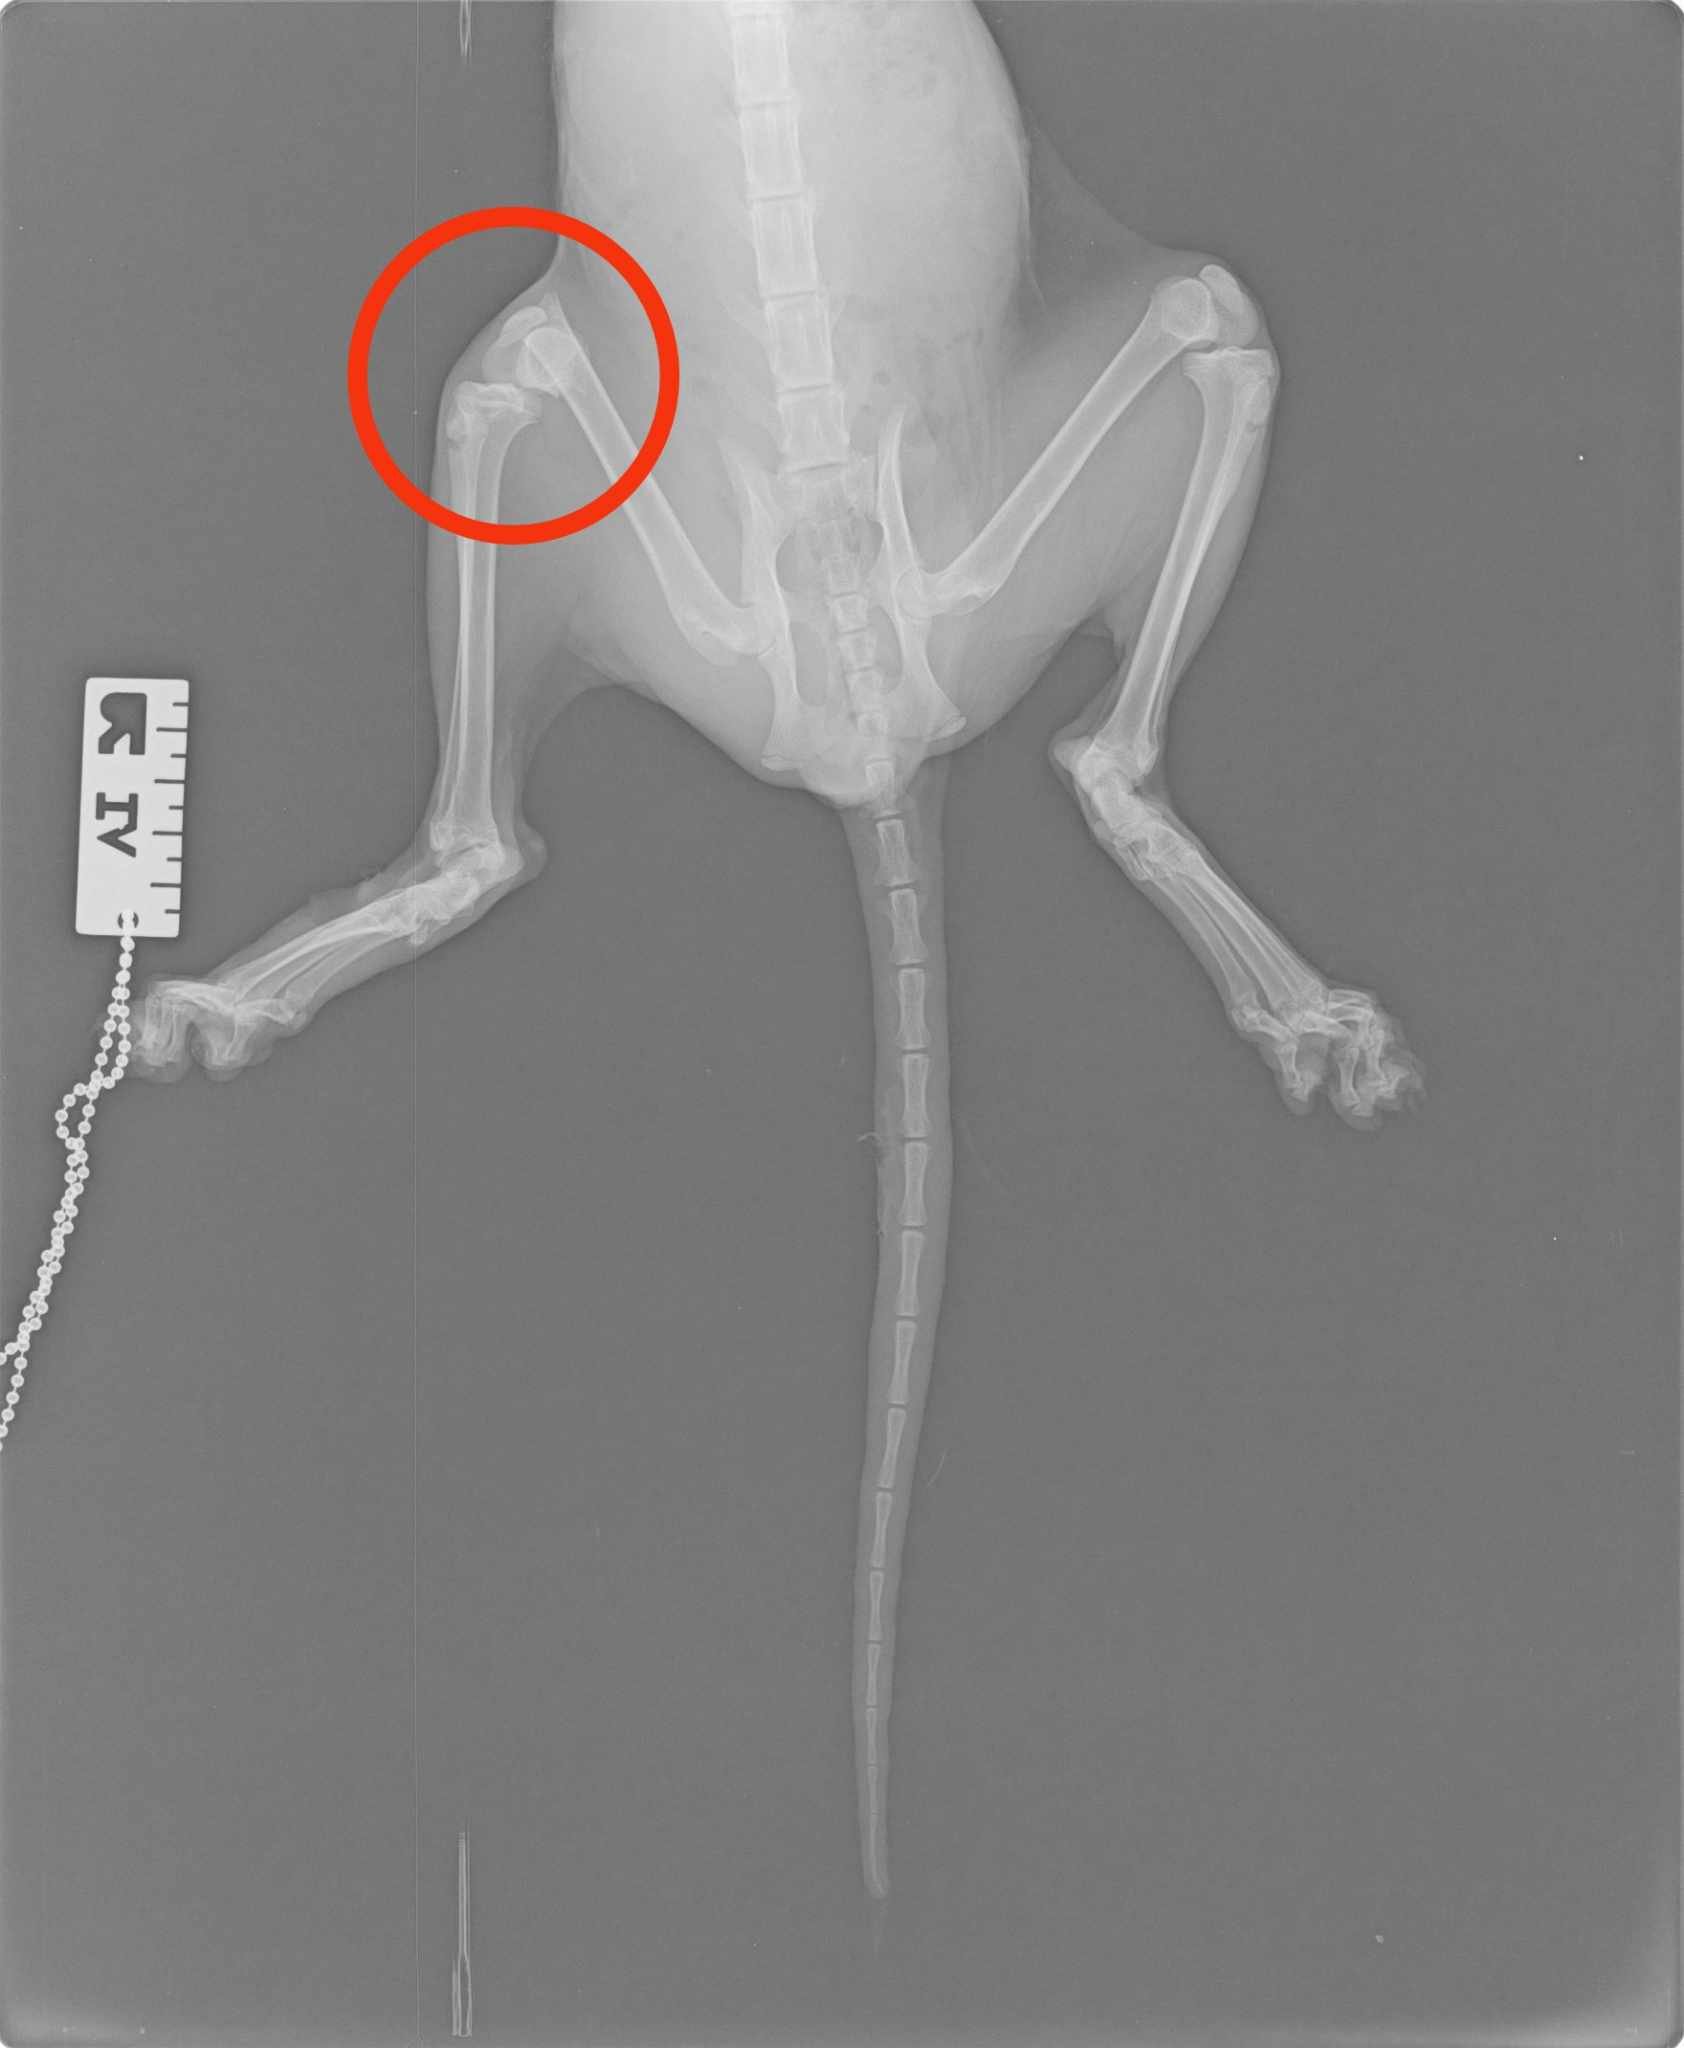

Billy is just a 6 month old kitten but his life has already been full of difficulties and hardships. Billy got trapped in the engine of a car and somehow he was lucky enough not to get minced. But he did sustain a bad wound in his tail and a very bad fracture on his right hind leg which requires orthopedic surgery or amputation. On top of that, he is suffering from a very bad infection of fungus causing him to lose entire tufts of his fur.